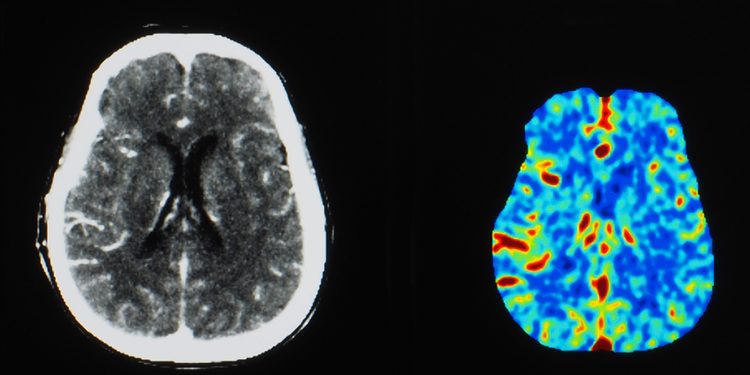

МРТ с контрастным усилением — распространенный вид диагностики; ежегодно во всем мире проводится более 30 миллионов процедур. В настоящее время для такой МРТ используются контрастные агенты на основе гадолиния (GBCA), но в последнее время возникают сомнения в их безопасности.

Что касается способности к контрастированию, ученые проверили ее в исследовании на мышах. Специалисты сравнили эффективность нового контрастного агента Mn-PyC3A с двумя современными GBCA (Gd-DOTA и Gd-EOB-DTPA) в обнаружении опухолей на мышиной модели рака молочной железы и метастатического рака печени.